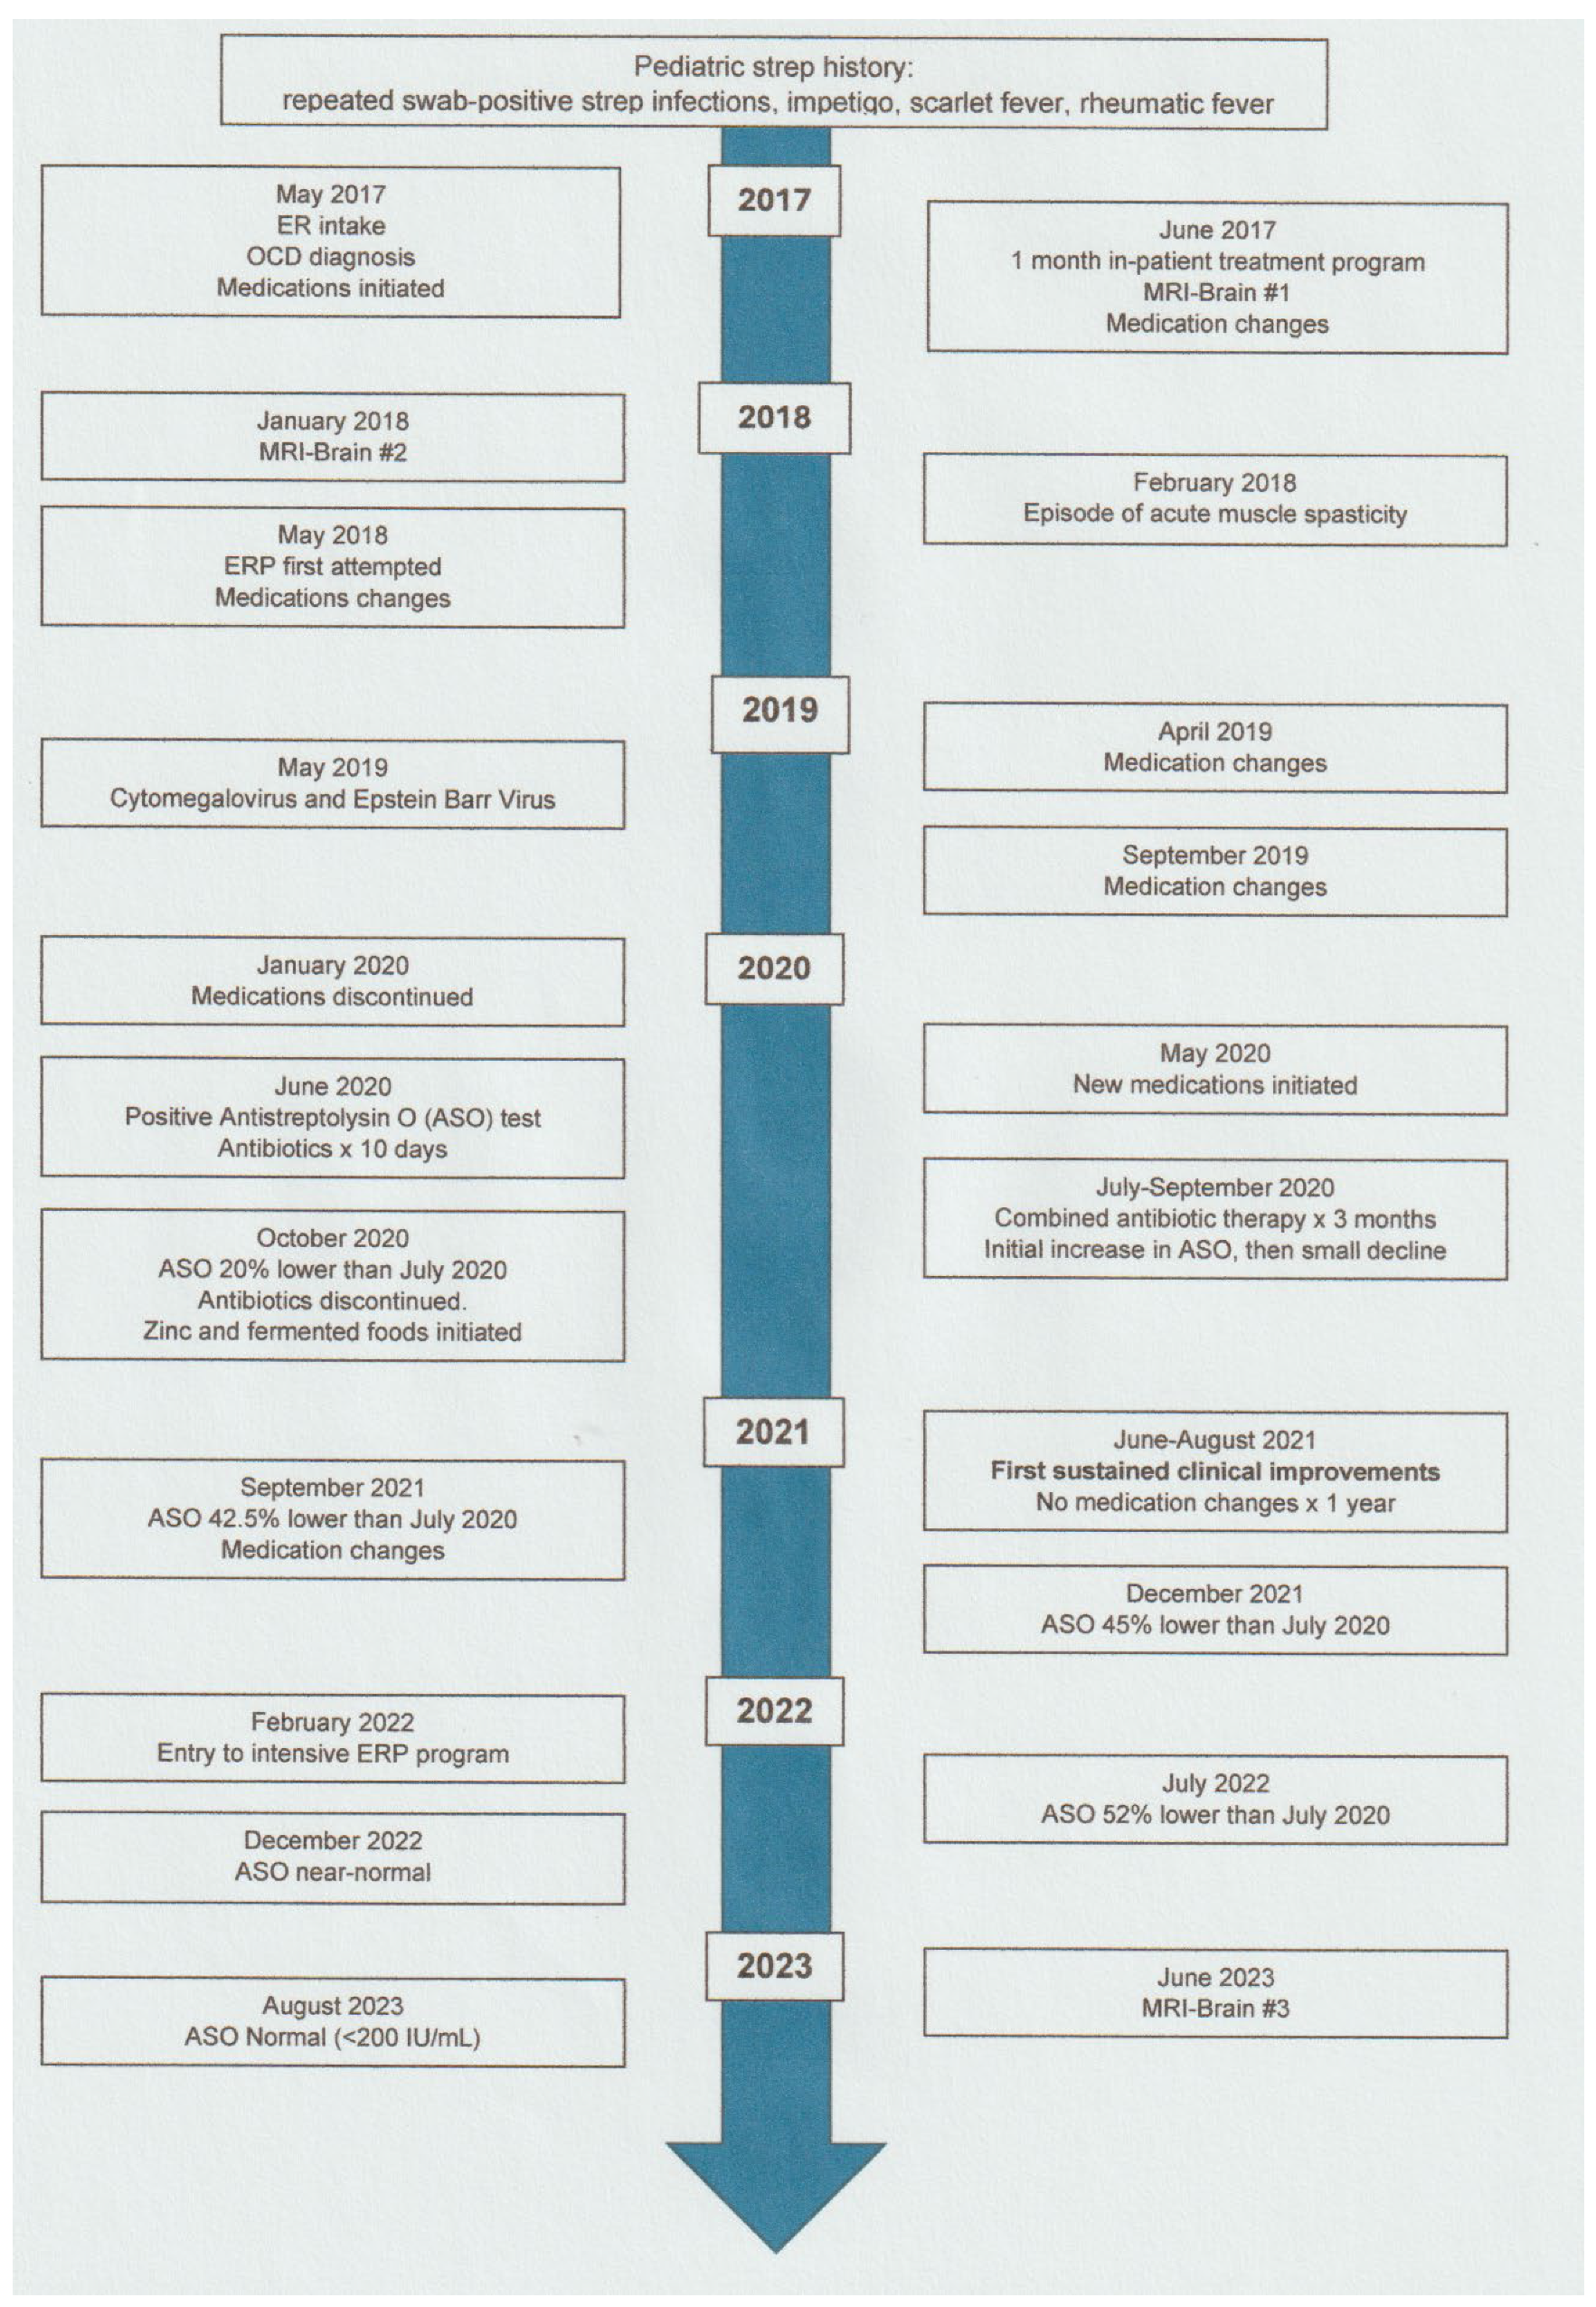

2. Case Report